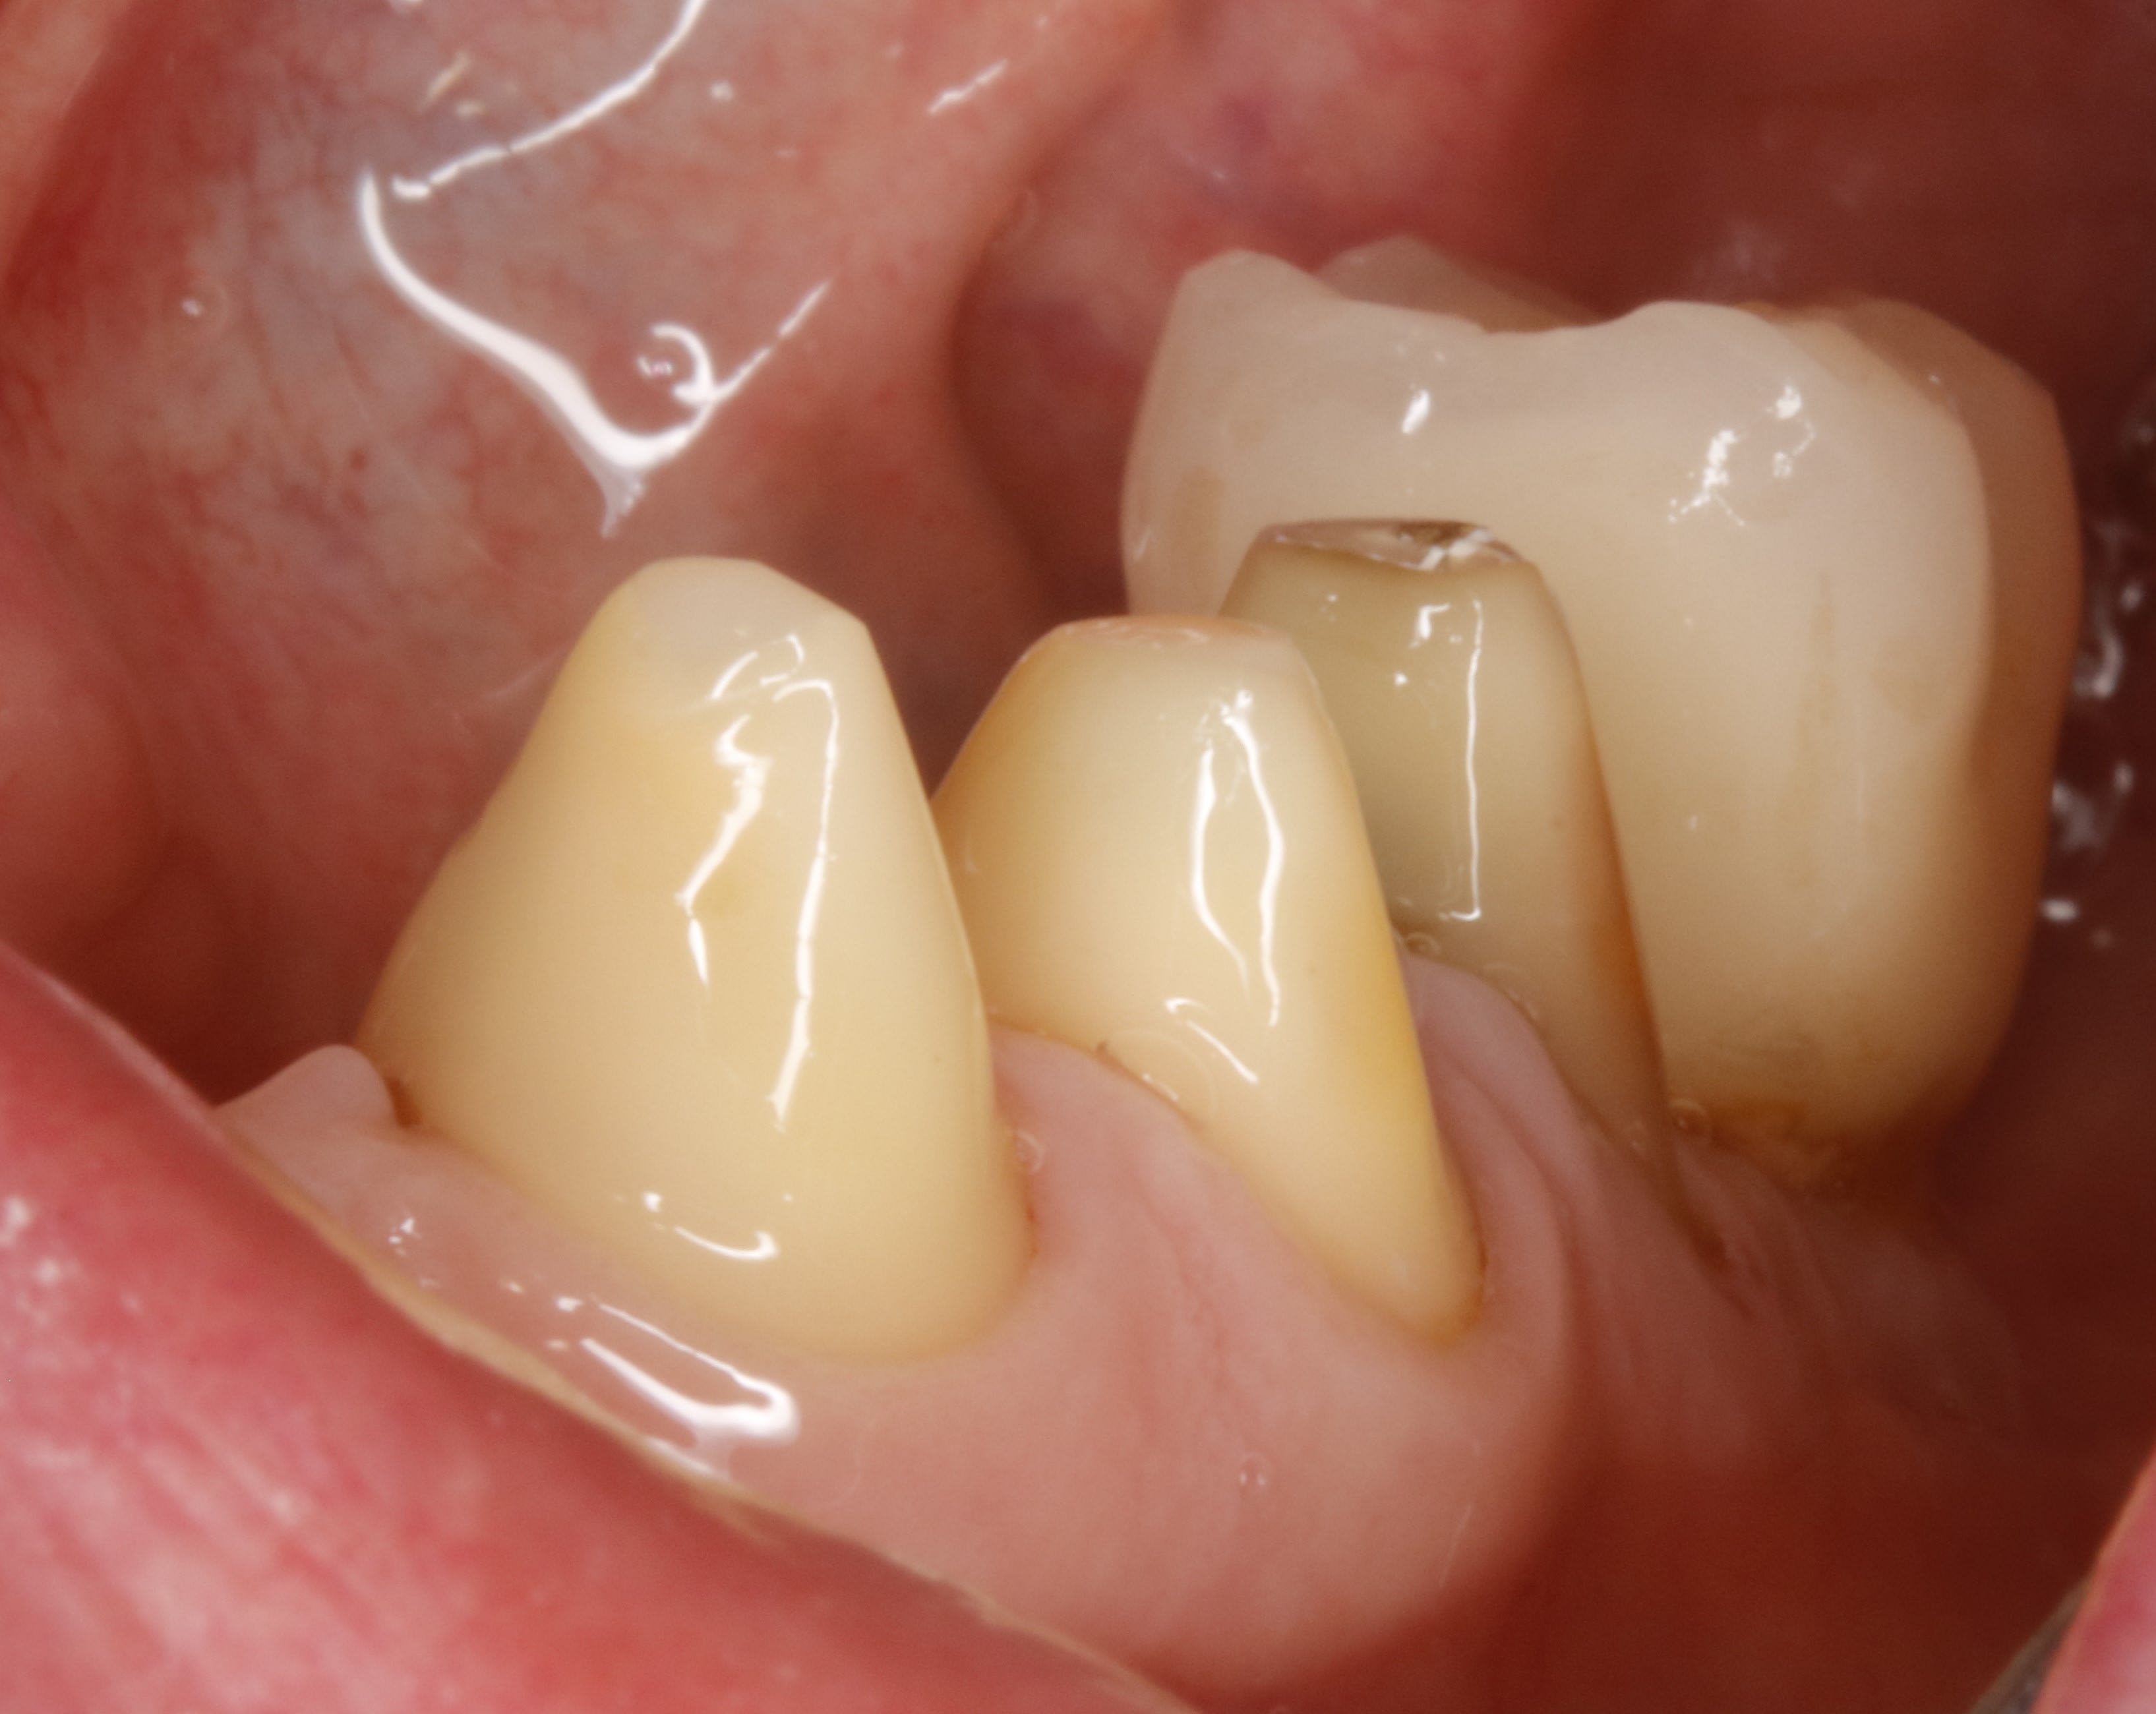

tourne et vire y a que ça qui me plait , le bridge de contention du bas .

toutes les dents qui bougent à mort , les incisives qui se font la malle , les gencives explosées et gros pb occlusal bien sur .

apres extractions et endos zing zing les tailles .

ici les tailles ont duré 3 mois pour en arriver là .

3 mois pour tailler .

non , on va le dire différemment, 3 mois pour arriver au niveau des limites définitives .

Chaques fois un petit coup pour arriver au niveau gingival cicatriciel du jour .

4 fois y compris les prétailles en unitaire avant les extractions de 41,42, 31,32 et 46

dans les 4 fois , en plus des tailles des moignons en totalité je compte aussi les tailles des racines et de gencive qui me permettent de faire de l assainissement parodontal .

Mais sinon , je ne comptais pas parler de prothèse mais de taille .

Il n y a personne ici qui se régale de tailler ?